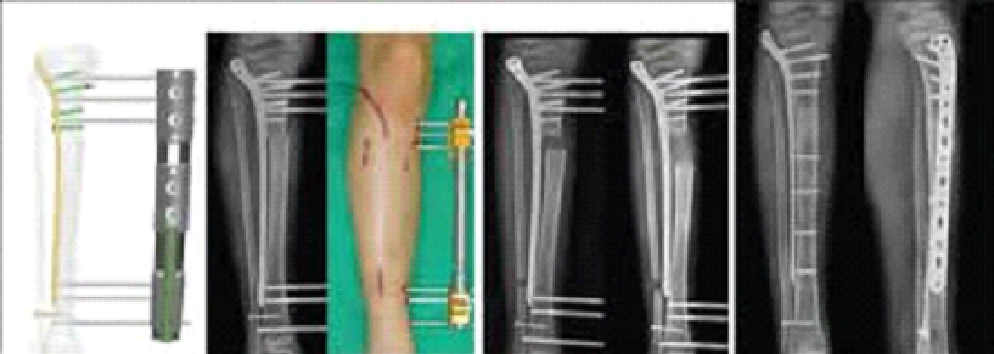

LOP (lengthening over plate)

Dr.Jijeesh